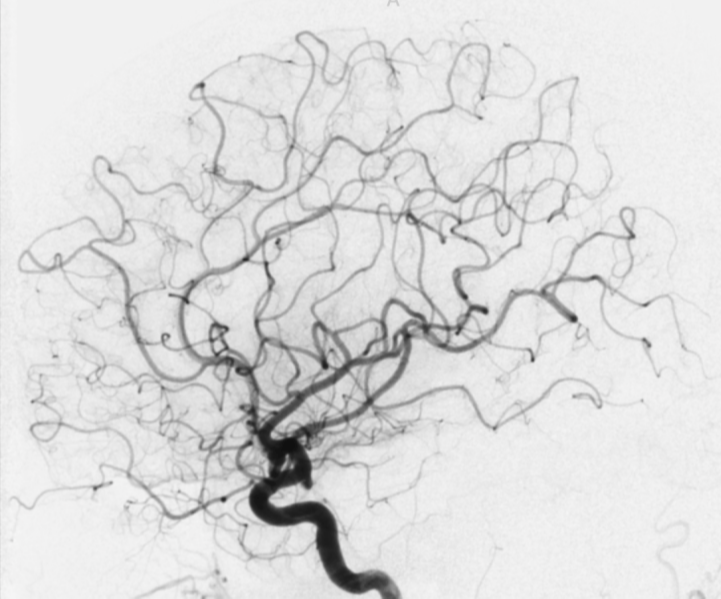

Angiografia:

exame padrão ouro para doenças

vasculares do cérebro.

A angiografia é o exame “padrão ouro” no diagnóstico de doenças vasculares como aneurisma cerebral, malformação arteriovenosa cerebral, dissecção arterial, estenose de artéria carótida e AVC. O procedimento também é utilizado no planejamento neurocirúrgico, podendo ser realizado por craniotomia, por via endovascular ou através da radiocirurgia, proporcionando uma intervenção mais precisa e segura.

A angiografia é realizada com um cateter diagnóstico que é introduzido por uma artéria do braço ou perna. O cateter é posicionado nas artérias do pescoço que seguem para o cérebro. Em seguida, pelo cateter, é injetado o contraste iodado não iônico que cora os vasos sanguíneos (artérias e veias) do cérebro e da medula espinhal. Após a injeção do contraste são adquiridas imagens de alta resolução feitas pela máquina de hemodinâmica.

O procedimento é minimamente invasivo e proporciona uma excelente visão em tempo real dos vasos sanguíneos, responsáveis pela vascularização do cérebro e da medula espinhal. A angiografia cerebral ou a angiografia medular oferecem as melhores condições para a definição do diagnóstico correto e preciso de uma patologia vascular, e também proporcionam uma melhor visualização para a abordagem adequada no tratamento.